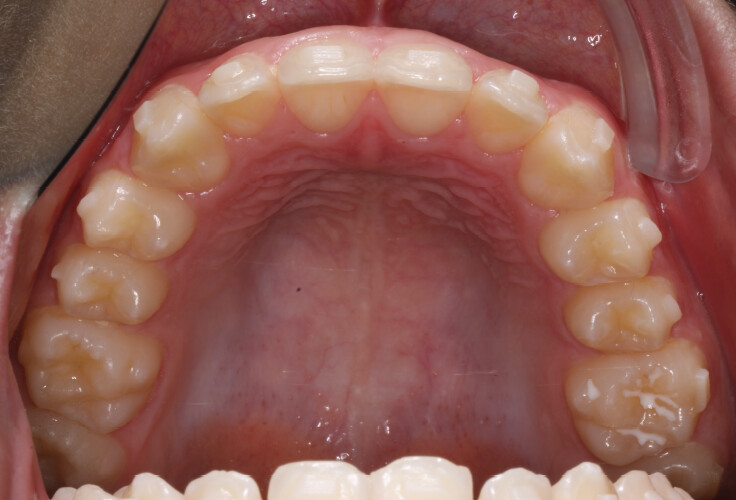

The treatment was carried out using Angel Aligner clear aligners, with strict adherence to periodontal biological limits. Both maxillary incisor intrusion and transverse expansion were carefully monitored throughout the process to prevent any periodontal compromise. Mandibular advancement was initiated directly from the 4th aligner using advancement blocks, eliminating the need for a preliminary pre-advancement phase. The patient was at the CS3 stage of cervical vertebral maturation, corresponding to the pubertal growth spurt, a biologically favorable period for condylar remodeling and skeletal adaptation. A total of 35 aligners with advancement blocks were used, followed by 10 additional aligners incorporating Class II elastics on Angel Buttons to finalize rotations and alignment. With weekly aligner changes, the overall treatment duration was approximately 45 weeks (10 months), aligning with the expected biological timeline for condylar remodeling. For mandibular anterior intrusion, the Frog Protocol combined with interproximal reduction (IPR) achieved complete leveling of the Curve of Spee.